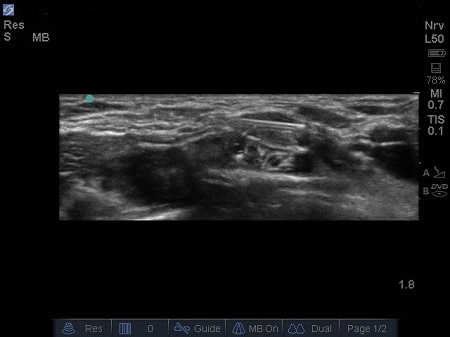

- The first structure to locate is the round pulsating hypoechoic subclavian artery (A), lying on top of the hyperechoic first rib (R). Use Doppler to assess for vessels. See Fig. 2.

Fig. 2. Bidirectional Doppler used here to highlight the subclavian artery.

- The subclavian vein (V) is found more medially to the artery. The anterior scalene muscle inserts onto the first rib between these two vessels (A and V), but occasionally there are anatomical variations (4) where both vessels are together between the insertions of both the scalene muscles (anterior and middle ones).

Fig. 3. Sonoanatomy of infant supraclavicular region. A – Subclavian artery. B – brachial plexus, P – pleura, R – first rib, V – subclavian vein

- Lateral and above the artery sit a bundle of round hypoechoic circles (“bunch of grapes” or “cluster of bubbles”) – the brachial plexus, at this level, the plexus will be configured as trunks and/or divisions.

- It may be possible to identify the hypoechoic nodules surrounded by a hyper-reflective fascial sheath.